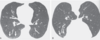

Fig. 3.7 Atelectasia adhesiva y cicatrizante después de la radioterapia. Una tomografía computarizada (A) muestra una masa en el lóbulo superior derecho, que se ha demostrado en una biopsia pulmonar que es carcinoma pulmonar. El tamaño de los lóbulos superiores es bastante simétrico. Una tomografía computarizada (B) 6 meses después de la radioterapia muestra extensas opacidades en vidrio esmerilado en el lóbulo superior derecho en el portal de radiación, características de la neumonitis por radiación. Una tomografía computarizada (C) 2 años después muestra una apariencia típica de fibrosis por radiación (citatasia por cicatrización) con bordes exteriores rectos (flechas). Nótese la presencia de bronquios dilatados y distorsionados dentro de las áreas de fibrosis (bronquiectasias de tracción) y sobreinsuflación compensatoria del pulmón adyacente. (D) Otro paciente 2 años después de la radioterapia por cáncer de pulmón del lóbulo superior derecho muestra atelectasia cicatricial grave del lóbulo superior derecho; Hay desplazamiento posteromedial y superior de la fisura mayor derecha (flechas)